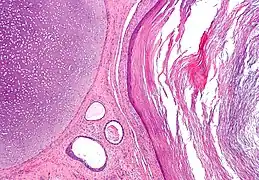

Coloration à l'hématoxyline et à l'éosine

- Certains tératomes produisent un mélange de tissus mûrs et bien différenciés : épithélium respiratoire, follicule pileux ; tissu adipeux ou tissu nerveux mûr.